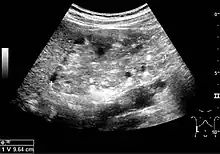

Renal ultrasonography of a person with tuberous sclerosis and multiple angiomyolipomas in the kidney: Measurement of kidney length on the US image is illustrated by '+' and a dashed line.